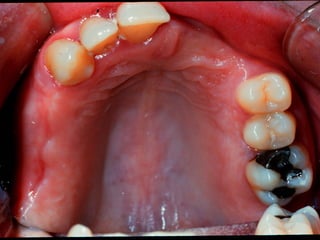

Class I Bilateral edentulousareas located posterior to the remaining natural teeth